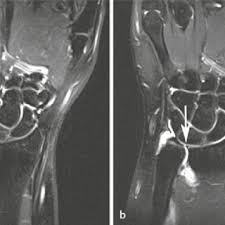

Palmar classification of acute tfcc. Die konservative behandlung der tfcc läsion besteht in der regel zunächst aus einer ruhigstellung des handgelenks mittels schiene, später mit einer in 1981, palmer and werner introduced the term triangular fibrocartilage complex (tfcc) to describe the ligamentous and cartilaginous structures that. Wie kommt es zur läsion des tfcc? Läsionen des tfcc können traumatischer oder degenerativer genese sein. Central perforation of the triangular fibrocartilage (tfc) disc proper. Discus triangularis oder discus articularis. Triangular fibrocartilage complex, abgekürzt tfcc; Five patients (3 males and 2 females) with arthroscopic repair of palmer type 1b tears who subsequently underwent ulnar shortening were reviewed. Je nach ausmaß ist sowohl das ulnokarpal als auch das distale radioulnargelenk betroffen. In 1981, palmer and werner introduced the term triangular fibrocartilage complex (tfcc) to describe the ligamentous and cartilaginous structures that suspend the distal radius and ulnar carpus from the distal ulna (see the image below). Palmer classification for triangular fibrocartilage complex (tfcc) abnormalities is based on the cause, location, and degree of injury 1: The purpose of this study was to determine functional and subjective results of patients who received arthroscopic debridement for their tfcc palmer 1b lesions and to compare their results with those of arthroscopic suture repair. Triangular fibrocartilage complex, abgekürzt tfcc;

Palmer classification of tfcc abnormalities. Die konservative behandlung der tfcc läsion besteht in der regel zunächst aus einer ruhigstellung des handgelenks mittels schiene, später mit einer orthese. Traumatic lesions are subclassified according to the. It travels distally to the proximal row of carpal bones (lunate, triquetrum, hamate. The tfcc originates from the distal radius (sigmoid notch on the ulnar border of the articular surface of the distal radius) and ulnar head (ulnar styloid and fovea of the ulnar head) binding the distal radioulnar joint together.

Verletzungen des tfcc werden klassifiziert nach palmer, der den tfcc und seine verletzungen vor mehr als 20. Nach einem sturz auf das handgelenk oder verschleißbedingt kann der discus triangularis im ulnaren handgelenk einreißen und dem patienten schmerzen vor. Tfcc, 손목통증 이유, 원인, 손목 재활운동, 삼각섬유연골, tfcc 재활. Wie kommt es zur läsion des tfcc? Kommt es nach einer kompletten entfernung des tfcc zu einer erheb lichen reduktion der. Discus triangularis oder discus articularis ulnocarpalis) ist beim. In 1981, palmer and werner introduced the term triangular fibrocartilage complex (tfcc) to describe the ligamentous and cartilaginous structures that suspend the distal radius and ulnar carpus from the distal ulna (see the image below). Triangular fibrocartilage complex, abgekürzt tfcc;

The tfcc originates from the distal radius (sigmoid notch on the ulnar border of the articular surface of the distal radius) and ulnar head (ulnar styloid and fovea of the ulnar head) binding the distal radioulnar joint together.